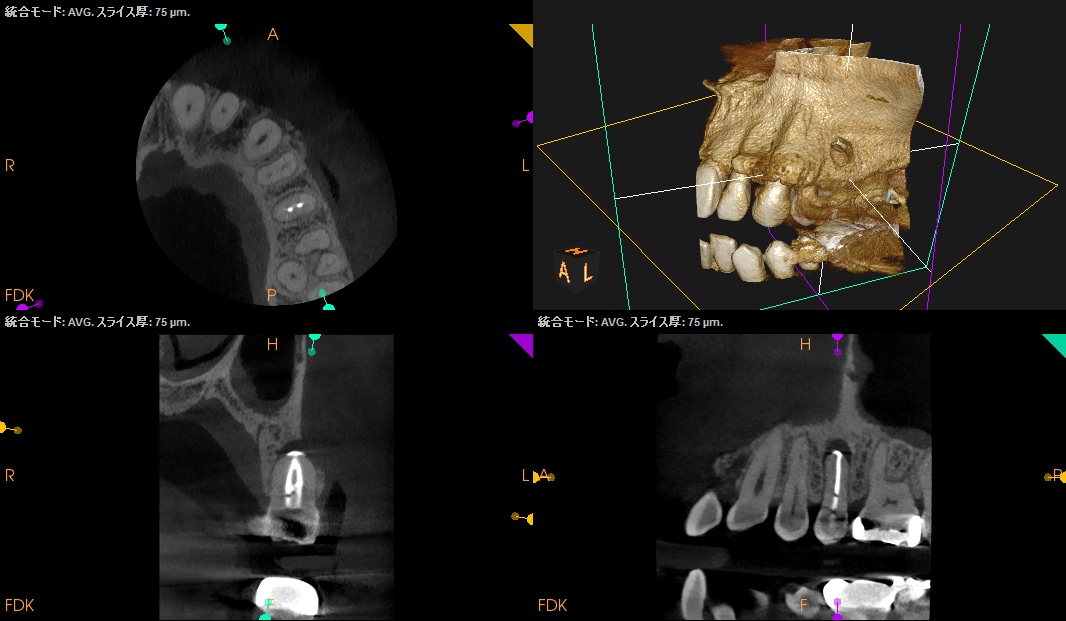

ペリオの問題がない歯だが、PAを撮ると

大きな根尖病変が#13のApex周囲にある。

またCBCTを撮影すると、

B

P

歯槽骨は溶けて#13のApexが口腔内に露出しかけている。

これが圧痛の原因になるのは間違いないだろう。